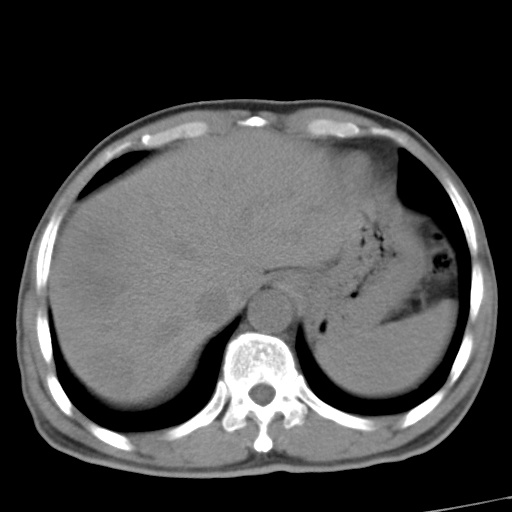

标题: CT17975:请求会诊。男、57岁。上腹部胀痛2天。临床诊断:糜 [打印本页]

标题: CT17975:请求会诊。男、57岁。上腹部胀痛2天。临床诊断:糜

肝脏多发类圆形低密度影,考虑肝脏转移瘤,肝胃韧带一淋巴结肿大,原发?胃癌?

考虑胃癌并肝脏及腹膜后淋巴结转移;不排除淋巴瘤。

肝内转移瘤,腹腔及腹膜后淋巴结转移。